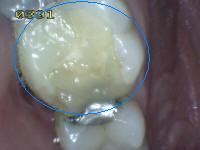

3. CARIES CON EXPOSICIÓN DENTINA

1. CAVIDAD DETECTABLE EXPONIENDO DENTINA

2. HALLAZGO CLÍNIICO:

1. cavidad en esmalte, con exposición de dentina

2. DIAGNÓSTICO

1. lesión cariosa cavitacional con exposición de dentina

2. TRATAMIENTO

1. operatoria

2. CRITERIO DE DIAGNOSTICO

1. cavidad detectable con dentina visible esmalte opaco o decolorado exponiendo dentina

1. ICDAS 5